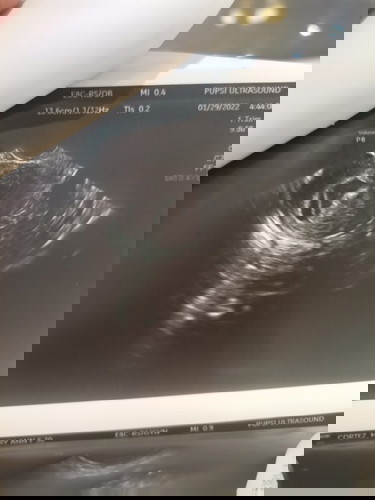

Hi Momshies, I'm expecting for twins. Kaso may bleeding😞? Nati-take ako Duphaston as per my OB.....

Meron ba dito ng Katulad ko? I'm 8weeks pregnant.

I had spotting at 9 weeks when I had my twins din before. It turned out, I had Totalis Placenta Previa. Asked your OB about your TVS result.